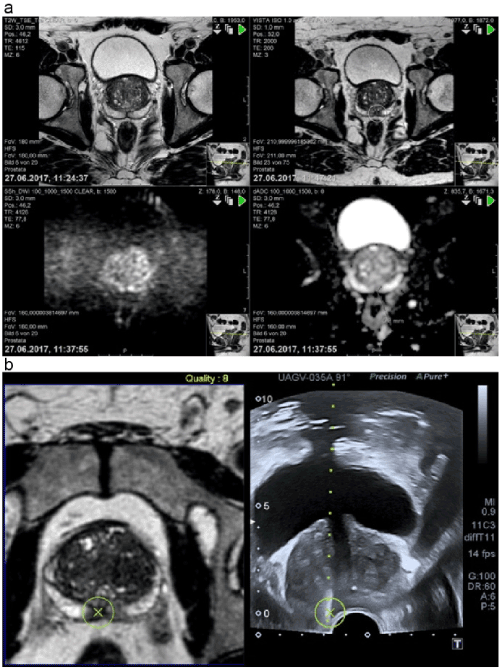

All patients underwent mpMRI performed on a 1.5-Tesla MR scanner (Philips Achieva Version 2 Series, Phillips, Amsterdam, The Netherlands) using a multichannel external phase array body coil, including T2-weighted imaging (T2WI) dynamic contrast–enhanced and diffusion-weighted imaging (DWI). The imaging protocol of PIRADS version 2 was followed according to the following recommendations of the American College of Radiology (ACR): reference slice thickness, 3 mm and field of view, 160 mm for DWI and 180 mm for T2WI in three planes. Further, we used four B values (0, 100, 1000, and 1500 s/mm2) for interpreting DWI. The results were analyzed and classified by experienced uroradiologists. DWI and T2WI were used for analyzing the peripheral zone (PZ) and transitional zone (TZ), respectively, and notable regions of interest (ROIs) were given an MRI suspicion score according to the PIRADS 2 scoring system following the ACR/European Society of Urogenital Radiology recommendations [17]. The lesions detected in the TZ were assessed in axial, sagittal, and coronal planes, while those detected in the PZ were assessed only in the axial plane. The lesions were scored from 1 to 5, with 1 indicating the lowest suspicion of PCa. The TZ in the T2WI sequence was classified as PIRADS 1 if homogeneous intermediate signal intensity/normal was noted; PIRADS 2, circumscribed hypointense or heterogeneous encapsulated nodules/benign prostatic hyperplasia; PIRADS 3, heterogeneous signal intensity with obscured margins and also includes others that do not qualify as PIRADS 2, 4, or 5; PIRADS 4, lenticular or non-circumscribed, homogeneous, moderately hypointense and <1.5 cm in the greatest dimension; and PIRADS 5, same as 4 except with ³1.5 cm in the greatest dimension or definite extraprostatic extension/invasive behavior. The PZ in the DWI sequence was classified as PIRADS 1 if no abnormality on apparent diffusion coefficient (ADC) and a high b-value on DWI were noted; PIRADS 2, for indistinct hypointensity on ADC; PIRADS 3, for focal mildly/moderately hypointense on ADC and isointense/mildly hyperintense on high b-value DWI); PIRADS 4, for focal markedly hypointense on ADC and markedly hyperintense on high b-value DWI and with <1.5 cm in the greatest dimension; PIRADS 5, the same as 4 but with ³1.5 cm in the greatest dimension or definite extraprostatic extension/invasive behavior. The images were saved on a CD for transfer to the ultrasound system [18] (Figure 1a).

Figure 1. a) History of DWI b:0 (top right) where a suspicious area could be found; DWI b:1500 (top left) presents a typical hyperintense area right in the peripheral zone and the corresponding hypointense area in ADC (bottom right), which established the diagnosis of PIRADS 4. T2W image (bottom left) shows a possible lesion that is verified by DWI and ADC. b) The fusion of suspicious areas in MRI and the corresponding ultrasound with the region of interest. The result proves the MRI suspicion, Gleason score 8 (4+4).

Abbreviations: ADC, apparent diffusion coefficient; DWI, diffusion-weighted imaging; MRI, magnetic resonance imaging; PIRADS, Prostate Imaging Reporting and Data System

Biopsies were performed under antibiotic prophylaxis dependent on the results of rectal swab, and 93% of patients received flourochinolons. For patients with grade ³2 lesions on MRI, 3-5 targeted biopsy specimens were first obtained from the described and marked ROIs (Figure 1a and 1b.) and 12-core systematic biopsies were then performed independent of MRI results in the axial plane. The protocol entails that samples encompassing the bilateral anterior, apex, mid, base, and lateral locations be obtained [14]. A spring-loaded gun (18-Gauge needle) was used, and biopsies were performed using an end-fire transrectal probe (Toshiba 11c3) by a single urologist supported by two uroradiologists. The patients were in the lateral position and received local anesthesia according to the department’s protocol with a lidocaine suppository plus a periprostatic nerve block [15]. mpMRI and fPBx were performed with a 1–5-week interval. The specimens were graded based on the International Society of Urological Pathology and World Health Organization guidelines.